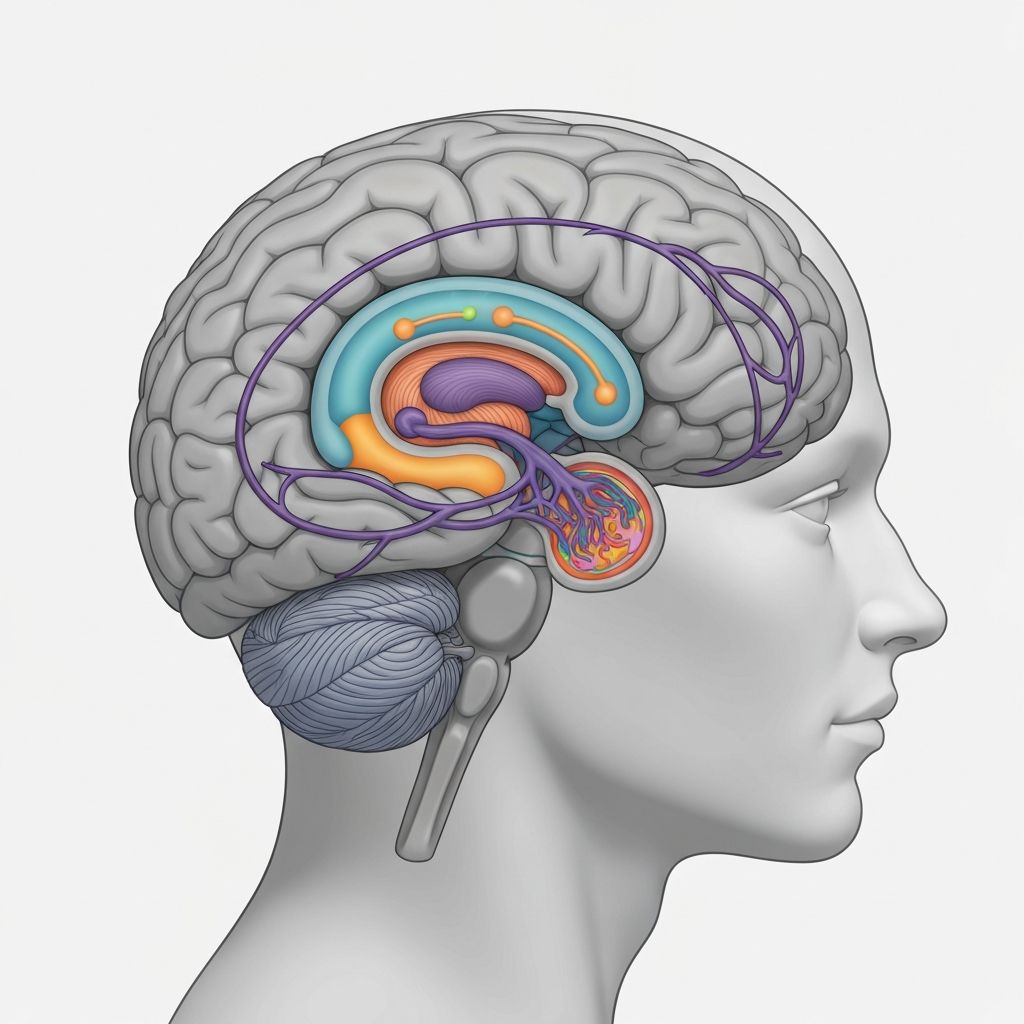

Die psychophysiologischen Mechanismen der Nahrungsaufnahme umfassen die bidirektionale Kommunikation zwischen dem zentralen Nervensystem und peripheren Organsystemen. Die Darm-Hirn-Achse spielt eine zentrale Rolle bei der Übermittlung von Sättigungssignalen.

Enterische Hormone wie Cholecystokinin, Peptid YY und Glucagon-like Peptide-1 werden nach Nahrungsaufnahme ausgeschüttet und wirken sowohl lokal auf den Vagusnerv als auch systemisch auf hypothalamische Rezeptoren. Diese Signale werden im Nucleus tractus solitarii verarbeitet.

Parallel dazu beeinflusst das autonome Nervensystem gastrointestinale Motilität und Sekretion. Sympathische Aktivierung hemmt die Verdauung, während parasympathische Aktivierung sie fördert. Diese Prozesse unterliegen einer komplexen neuroendokrinen Regulation.

Psychologische Faktoren wie Stress und Emotionen modulieren diese physiologischen Prozesse über kortiko-hypothalamische Pfade. Die Aktivierung der Hypothalamus-Hypophysen-Nebennierenrinden-Achse kann die hormonelle Regulation der Nahrungsaufnahme beeinflussen.